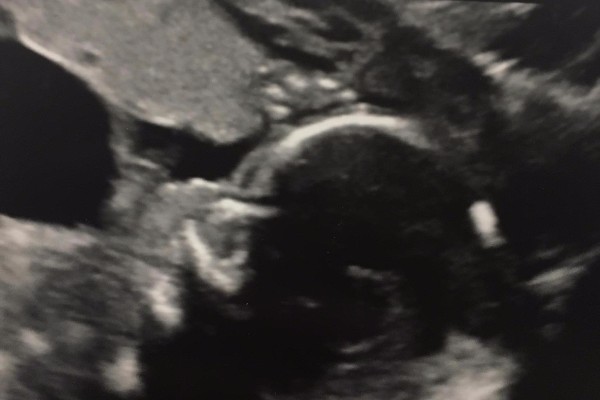

Our son Connor Isaac Houde was diagnosed with a rare disorder called prune belly syndrome. This is caused by a lower urinary tract blockage and keeps the baby from emptying his bladder. The bladder swells almost to the size of the mother's and causes pressure on the kidneys. Because of the pressure the kidneys have formed many cysts and he will have kidney problems at birth that may require dyalisis or transplants when he is old enough. Another issue with Connor is he has low amniotic fluid, this puts him at a higher risk of crushing his cord and will cause him to have underdeveloped lungs since he doesn't have as much room to move, expand and grow.